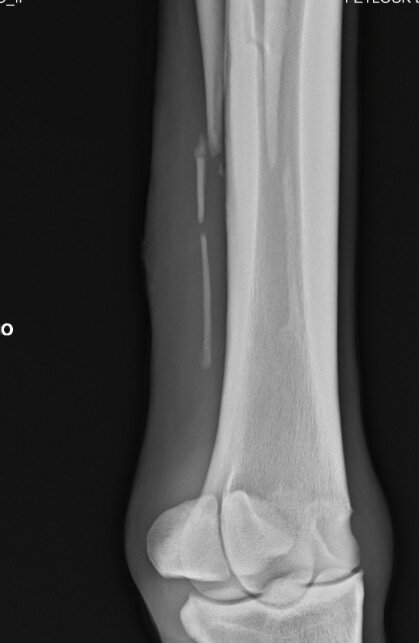

Ibbel schreef:Ik kan me niet voorstellen wat er mis zou kunnen gaan of wat de contra-indicaties van een operatie aan het griffelbeentje zouden kunnen zijn. Gebroken griffelbeentjes genezen niet, het afgebroken deel zal na verloop van tijd wel ingekapseld worden, maar dan heb je een los botfragment onderhuids zitten wat op allerlei structuren kan gaan drukken.

Cowgirl schreef:Ik zou die foto's opsturen naar een goede paardenkliniek en hun een oordeel laten maken.

Het ziet er behoorlijk heftig uit alhoewel ik ooit eens foto's gezien heb van en paard waarbij het gewoon verbrijzeld was..Daar konden ze niks mee, paard zou blijvende schade houden. Dier is dan ook ingeslapen.